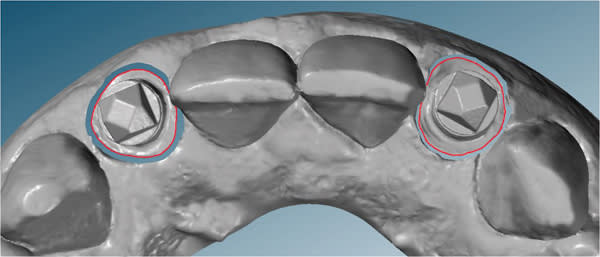

An intraoral digital impression of both custom scan bodies No. 7 and No. 10 was made with the itero digital impression system to create an STL file (Figure 17 and Figure 18). The custom shape of the scan bodies is clearly seen with red line margins in both the facial and occlusal views shown in Figure 19 and Figure 20.

The STL files were downloaded into the design program, creating a virtual working cast. The virtual cast illustrates the red margin line created by the custom scan body transfer, which will guide the laboratory in the designing of the definitive abutment margins (Figure 21). In addition, the STL files were utilized to fabricate a master cast created by CAD/CAM modeling of urethane material. The completed abutment design shows a dotted blue line depicting the margin line created from the custom scan body transfer (Figure 22). The virtual abutments’ STL files were then uploaded to the design software for CAD/CAM fabrication of the definitive zirconia abutments. After the abutments were received back at the laboratory, they were placed on the master cast, evaluated/modified (Figure 23), and scanned into prosthesis design software. The definitive prostheses were fabricated with zirconia copings and layered porcelain.